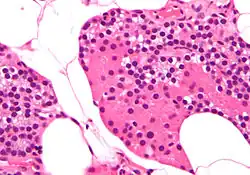

Célula oxífila (paratiroides)

En la glándula paratiroides, las células oxífilas de la paratiroides son más grandes y de coloración más clara que las células principales de la paratiroides.

Estas células se encuentran en grupos en el centro de la sección y en la periferia.[1][2][3][4] Las células oxífilas aparecen al comienzo de la pubertad, pero no tienen una función conocida. Con los escáneres de medicina nuclear, toman selectivamente el radiotrazador del complejo de tecnecio-sestamibi para permitir la delineación de la anatomía glandular.[5] Se ha demostrado que las células oxífilas expresan genes relevantes para las paratiroides que se encuentran en las células principales paratiroideas y tienen el potencial de producir factores autocrinos/paracrinos adicionales, como la proteína relacionada con la hormona paratiroidea (PTHrP) y el calcitriol.[6] Es necesario seguir trabajando para comprender plenamente las funciones de estas células y sus secreciones.